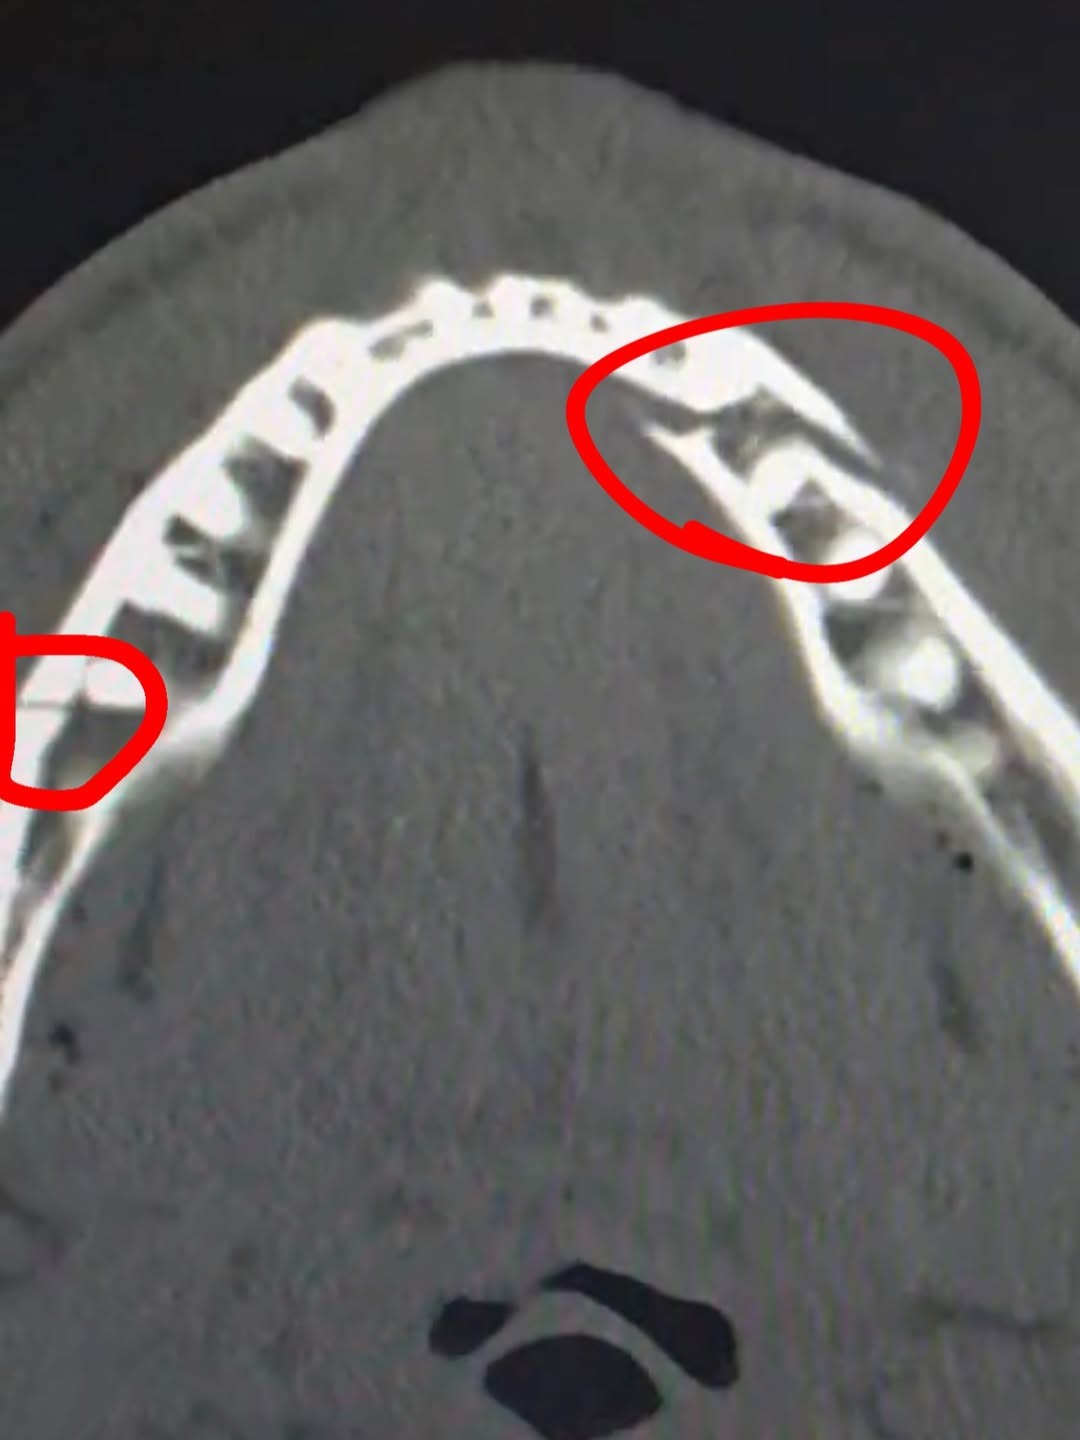

Jake Paul fratura a mandíbula em luta com Anthony Joshua; veja imagem

Jake Paul protagonizou o maior desafio da carreira nesta sexta-feira (19), e voltou a amargar um resultado negativo após 33 meses – o último revés do americano aconteceu em fevereiro de 2023. Em confronto contra o campeão olímpico e ex-campeão mundial, Anthony Joshua, Paul acabou nocauteado no sexto round. Além do resultado negativo, ele sofreu duas lesões na mandíbula. Por meio das redes socias, compartilhou a imagem do seu raio-x e ainda brincou com os fãs, afirmando que estaria pronto para enfrentar o ex-campeão mundial Canelo Álvarez.

– Mandíbula partida em dois. Me dê o Canelo em 10 dias – escreveu Paul.

Jake Paul sofre duas lesões na mandíbula em luta com Anthony Joshua